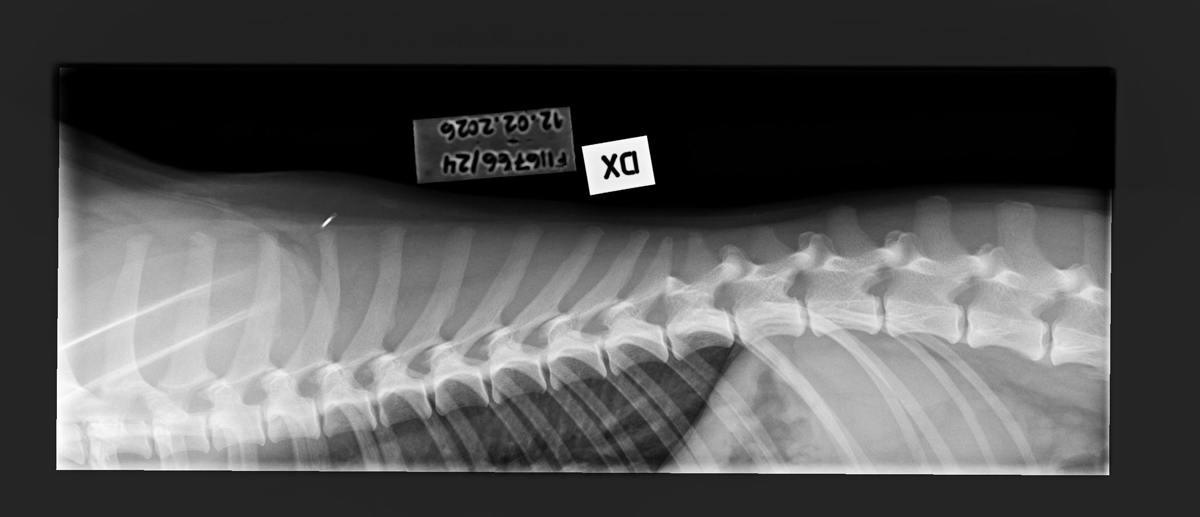

- Free of lumbosacral transitional vertebrae (LTV0)

- Free of spondylosis (SP0)

- Free of vertebral anomalies (VA0)

- Spine x-rays: 1, 2 ja 3